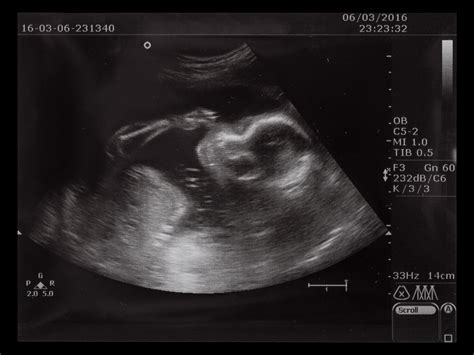

La curiosità di conoscere il prima possibile se il proprio bambino sarà un maschio o una femmina è una prerogativa della maggior parte dei genitori, desiderosi di anticipare una vita futura in rosa o in celeste, con tutte le conseguenze del caso, non ultimo la scelta del nome. Questa legittima curiosità ha portato alla diffusione di diverse teorie e metodi, tra cui la "Nub Theory". La Nub Theory, o teoria del tubercolo genitale, è quella teoria per cui si può conoscere il sesso del nascituro già dalla prima ecografia eseguita tra la sesta e la quattordicesima settimana di gravidanza.

Questa teoria è basata sull'osservazione che i tubercoli genitali delle femmine tendono a essere più piccoli e a puntare verso il basso, o ad essere paralleli alla colonna vertebrale, mentre quelli dei maschi tendono a essere più grandi e a puntare verso l'alto. La grande differenza, nel tubercolo genitale nei maschi e nelle femmine, risiede nell'angolo che questo realizza con l'asse del corpo fetale. Nel dettaglio, il principio funziona così: se il tubercolo crea un angolo superiore ai 30 gradi, si tratta di un maschio; se l'angolo è inferiore ai 10 gradi, è femmina. Esiste una "fascia grigia" fra 10-30 gradi in cui non si riesce a predire il sesso con accuratezza.

Per visualizzare correttamente questa piccola sporgenza e valutarne l'angolazione, è necessario che l’ecografia mostri il bambino di profilo e che la colonna vertebrale sia ben visibile. L’attendibilità della Nub Theory è attestata intorno al 91.5% ma solo quando la misura della lunghezza del feto (il CRL) è maggiore di 60 mm in un’epoca gestazionale superiore alle dodici settimane. Secondo le statistiche, la Nub Theory è affidabile al 75% dalla 12esima settimana e al 95% dalla 13esima. Tuttavia, è importante sottolineare che questa "nub theory" è attendibile solo se applicata da personale esperto e in una fase gestazionale più avanzata, generalmente dopo l'11a settimana.

Le discussioni online sono numerose e dettagliate. Molte future mamme si confrontano su ciò che il ginecologo ha detto durante la TN, ricordando che "quel coso che sporge in tutti (maschi e femmine) non è un pistolino!" ma è proprio il tubercolo genitale. Se è orizzontale, si trasformerà in "patata", mentre se è inclinato verso l'alto sarà un "vero pisello". Commenti come "I miei lo avevano diritto diritto in mezzo alle gambe… Che sarà???", "Ho visto un puntino bianco…. Non era né verticale né orizzontale… Quindiiiiiiii????", o "Bello in pole position tra le gambe!" riflettono la curiosità e talvolta la confusione generate da queste osservazioni precoci. Alcuni medici, di fronte all'insistenza, potrebbero dire "POTREBBE essere maschietto ma non mi prendo la responsabilità", riconoscendo la difficoltà di una previsione accurata così presto. Anche se in questo studio si precisa che nelle femmine il tubercolo genitale è sempre situato appena sotto l’attaccatura della coda, mentre nei maschi è sempre situato immediatamente dietro il cordone ombelicale, la distinzione angolare rimane il cardine della teoria.

it's a baby girl 🤱by 'Nub Theory' !! Ultrasound